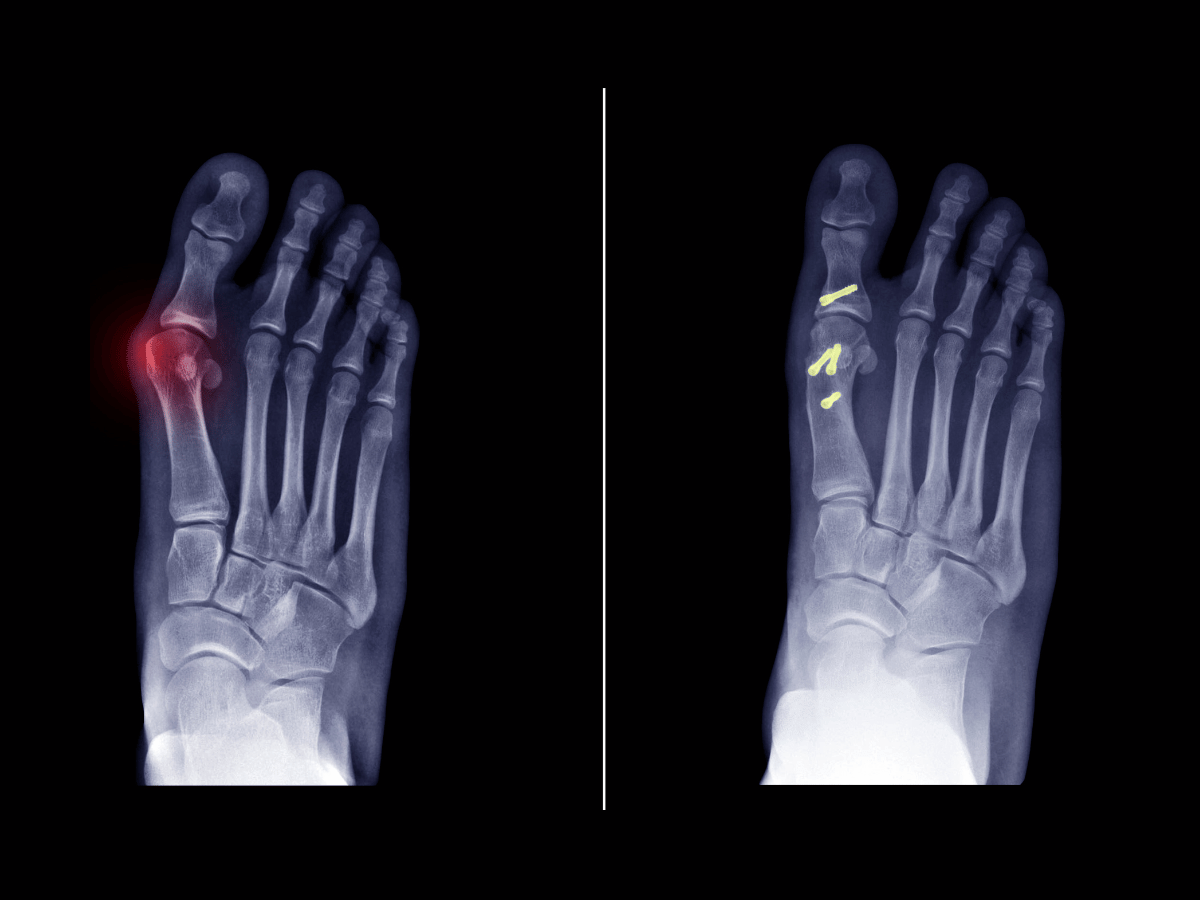

Bunions affect millions, creating discomfort and disrupting daily mobility. For years, bunion correction meant long recovery periods and invasive surgical techniques. But thanks to advanced methods like minimally invasive bunion surgery (MIS), that’s no longer the only path forward. At South Florida Multispecialty Medical Group (SFL Medical Group), we specialize in providing effective bunion […]